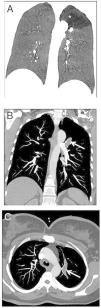

A 22-year-old woman was referred to our emergency radiology unit with sudden onset of shortness of breath and left-sided chest pain. The chest radiography revealed left hilar tubular opacite (arrow) and hyperaeration (asterisk) in the upper zone of the left lung (Fig. 1). The contrast enhanced computed tomography (CT) showed a non-contrast enhancing tubular mass that was seen extending from the left hilum, with surrounding hypoattenuation of the apicoposterior segment of the left upper lobe (asterisk), a finding indicative of hyperinflation (Fig. 2A). There was also no connection between the non-contrast tubular mass (arrows) and pulmonary artery of the apicoposterior segment in the left upper lobe (Fig. 2B–C). CT findings were also including mucocele and occlusion of the bronchus central to the mucocele. CT results (mucocele with hyperaeration of the adjacent lung parenchyma) were considered pathognomonic for bronchial atresia. Surgical treatment was no performed because the patient refused operation.

The reformat coronal CT at maximum inspiration (A) shows a non-contrast enhancing tubular lesion with surrounding hypoattenuation of the apicoposterior segment of the left upper lobe (asterisk), a finding indicative of hyperinflation. The coronal CT scan also demonstrates aerial trapping in the apicoposterior segment of the left upper lobe. The contrast enhanced maximum intensity projection images (B and C) reveal no connection between the non-contrast tubular lesion (arrows) and pulmonary artery of the apicoposterior segment in the left upper lobe.